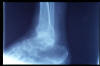

ACT espolón calcáneo y microcalcificaciones.